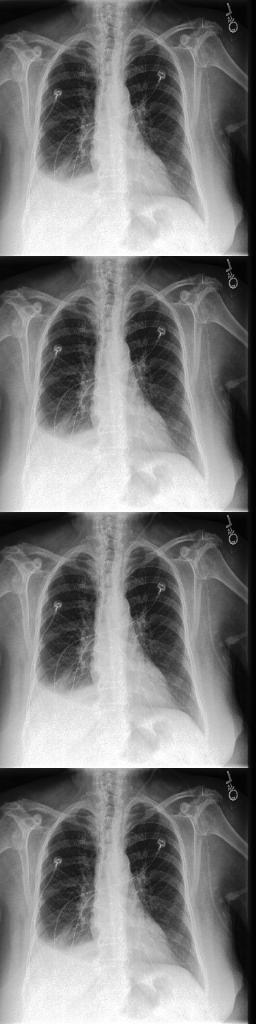

For the Chexpert dataset introduced in [12], we used a training set of 14179 images of healthy subjects and 16776 images of subjects that suffer from pleural effusions. The test and validation set each consist of 200 images for each class.

Refer to captionInput rpsubscript𝑟𝑝r_{p}Refer to captionOutput ahsubscript𝑎a_{h}Refer to captionDifference |d|𝑑|d|Refer to captionInput rpsubscript𝑟𝑝r_{p}Refer to captionOutput ahsubscript𝑎a_{h}Refer to captionDifference |d|𝑑|d|Refer to caption11100DeScarGANFP-GANVAGANVAE

Figure 6: Comparison of our DeScarGAN against FP-GAN, VAGAN and VAE for two samples of the Chexpert dataset.

DeScarGAN achieves better classification results than the pure classification networks Dclssubscript𝐷𝑐𝑙𝑠D_{cls} and Densenet169, indicating that the GAN mechanism supports the classification network. The results of the different methods are visualized in Figure 6. We observe that the VAE fails to detect pleural effusions. Although FP-GAN detects similar regions as our method, the generated maps appear blurry and mark regions outside the thorax. The additive map of VAGAN also outlines parts of the arms and upper chest as abnormal. Our method generates the most detailed difference map, not highlighting any regions outside the pleural space.